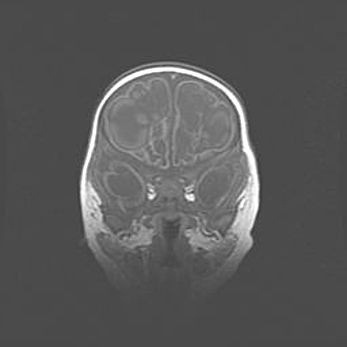

Аномалия Денди-Уокера. Признаки гипоплазии мозолистого тела.

Возраст: 5 месяцев 3 дня

Вес: 5550 г

Пол: мужской

Окружность головы: 39 см

Срок гестации: 40 недель

Аномалия Денди-Уокера – это порок развития головного мозга, для которого характерна триада симптомов: гипотрофия или аплазия червя мозжечка и/или полушарий мозжечка, расширение четвёртого желудочка с формированием ликворной кисты задней черепной ямки, гипертензионная гидроцефалия различной степени.

Гипоплазия мозолистого тела относится к дефектам внутриутробного этапа развития мозговой ткани, возникающим в процессе закладки структур головного мозга, что происходит на начальных этапах развития эмбриона.